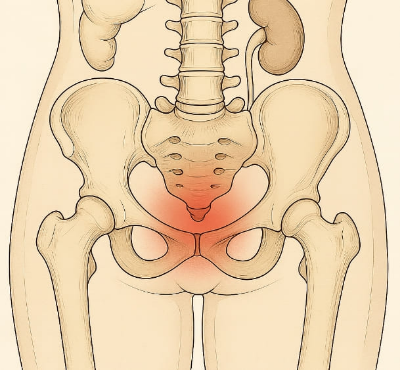

골반 통증은 하복부, 즉 배꼽 아래에서 고관절 위까지의 부위에서 발생하는 불쾌감이나 통증을 말합니다. 이 부위에는 생식기, 방광, 장, 골반 뼈와 근육, 신경 등이 밀집해 있어 다양한 원인으로 골반 통증이 발생할 수 있습니다. 골반 통증 원인을 명확히 아는 것은 정확한 진단과 치료로 이어지기 때문에 매우 중요합니다.

골반 통증 원인 분류

골반 통증 원인은 다음과 같이 분류할 수 있습니다.

- 부인과적 원인: 난소낭종, 자궁내막증, 골반염, 생리통 등